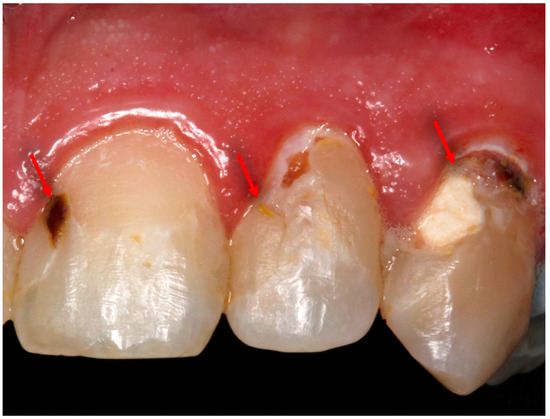

- Balhaddad, A.A.; Ibrahim, M.; Weir, M.D.; Xu, H.H.K.; Melo, M.A.S. Anti-Biofilm and Mechanically Stable Bioactive Composite for Root Caries Restorations. Dent. Mater. 2019, 35, e4–e5. [Google Scholar] [CrossRef]

- Balhaddad, A.A.; Ibrahim, M.S.; Weir, M.D.; Xu, H.H.K.; Melo, M.A.S. Concentration dependence of quaternary ammonium monomer on the design of high-performance bioactive composite for root caries restorations. Dent. Mater. 2020. [Google Scholar] [CrossRef]

- Wang, L.; Melo, M.A.S.; Weir, M.D.; Xie, X.; Reynolds, M.A.; Xu, H.H.K. Novel bioactive nanocomposite for Class-V restorations to inhibit periodontitis-related pathogens. Dent. Mater. 2016, 32, e351–e361. [Google Scholar] [CrossRef] [PubMed]